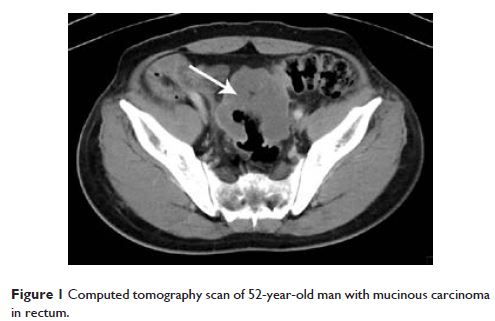

Case Report

- 作者:Yanmei Peng, Huijuan Cui, Zhe Liu, Daiwei Liu, Fan Liu, Yazhong Song, Hua Duan, Yuqin Qiu, Qiang Li

- 期刊:OncoTargets and Therapy